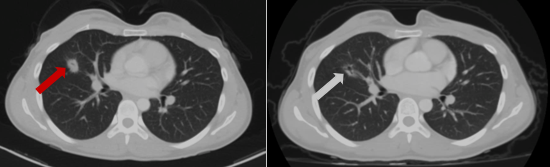

Sau đó bệnh nhân được chỉ định thêm các xét nghiệm cận lâm sàng khác. Trên phim chụp cắt lớp vi tính lồng ngực của bệnh nhân phát hiện khối u phổi dạng nang kích thước ~ 20x14mm ở thùy giữa phổi phải.

Hình 2. Hình ảnh khối u phổi phải trên phim chụp Cắt lớp vi tính ngày 27 tháng 10 năm 2022 (mũi tên).